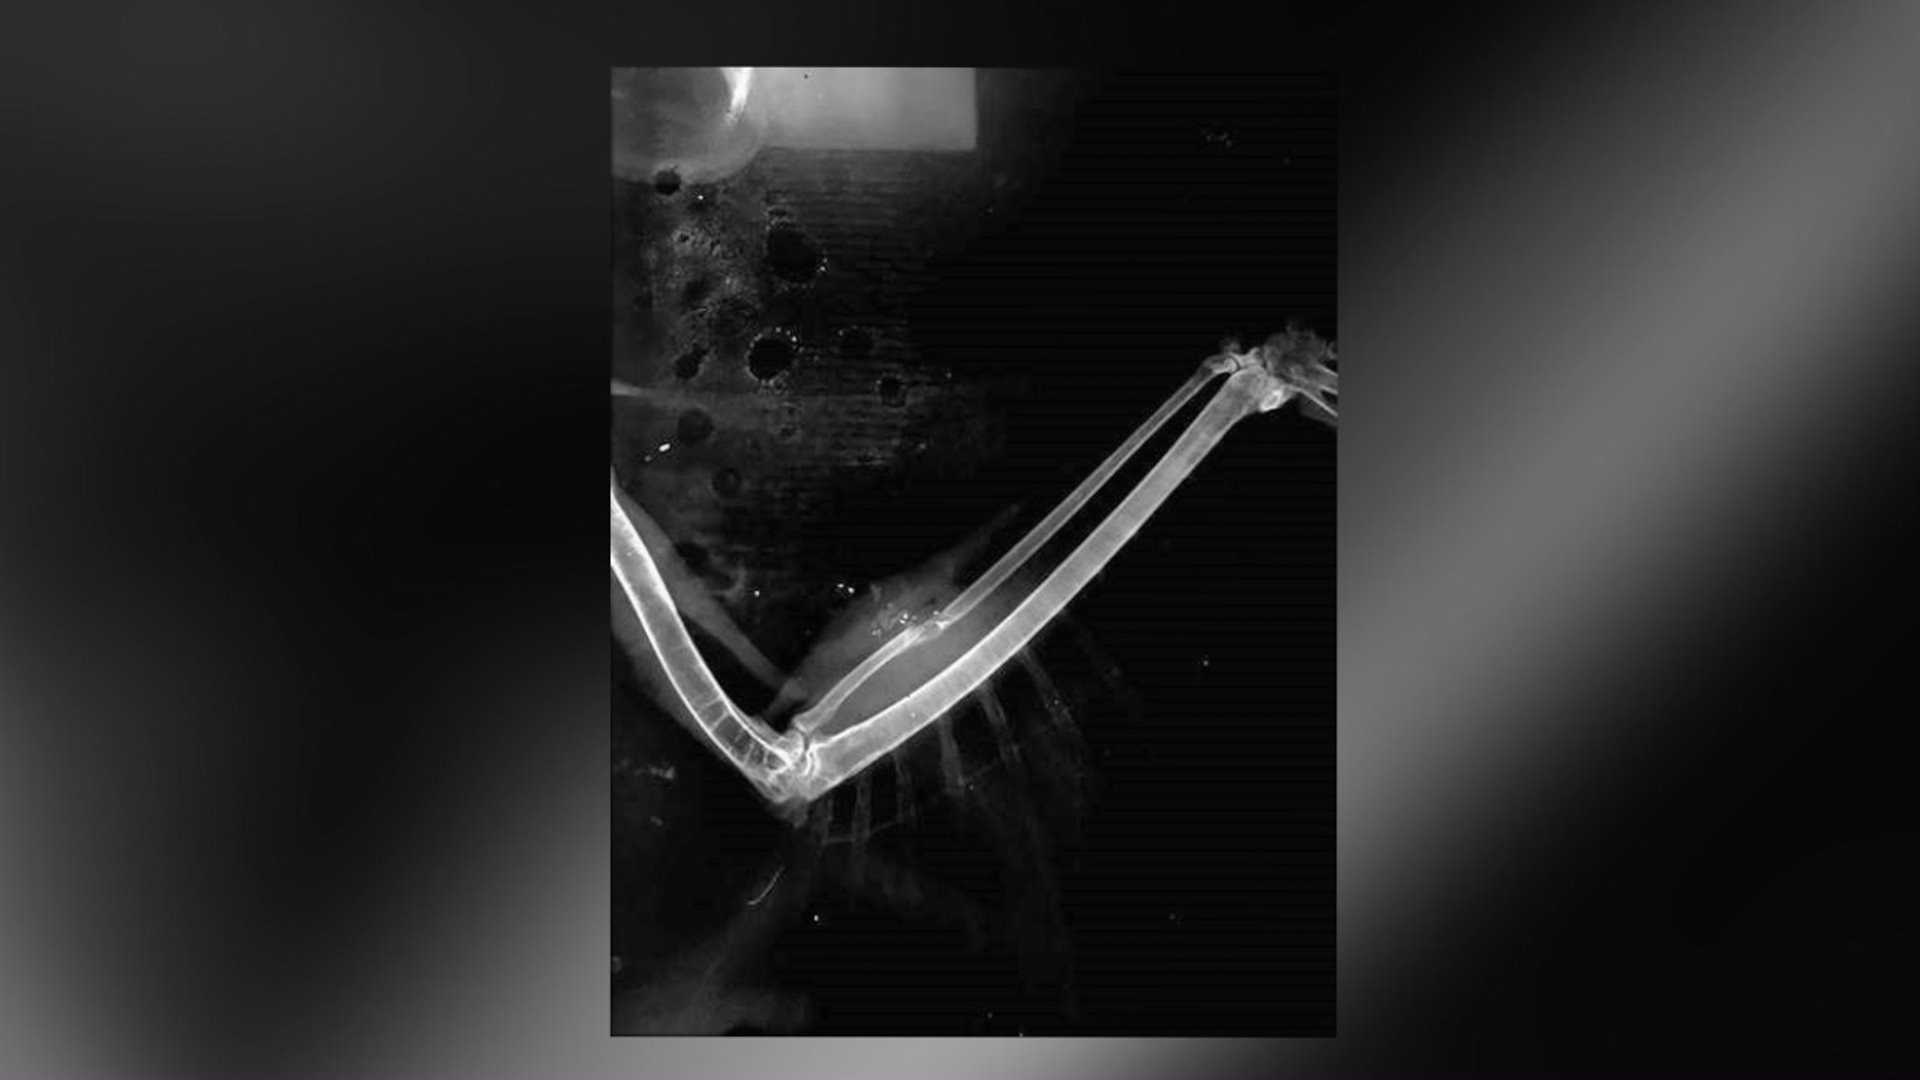

Red-tailed hawk released into the wild after someone shot her